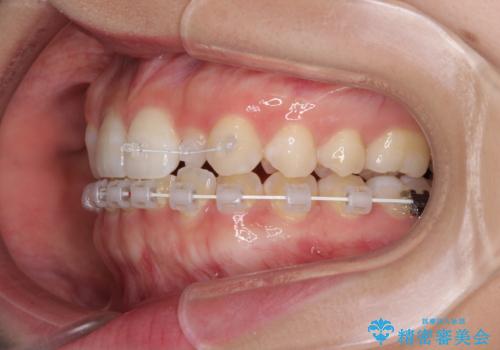

下顎は叢生が強かったため、奥歯までワイヤーを装着し、上顎は前歯の一部のみ気になっていたので、その部分にだけワイヤー装置を装着することとしました。

- 審美装置